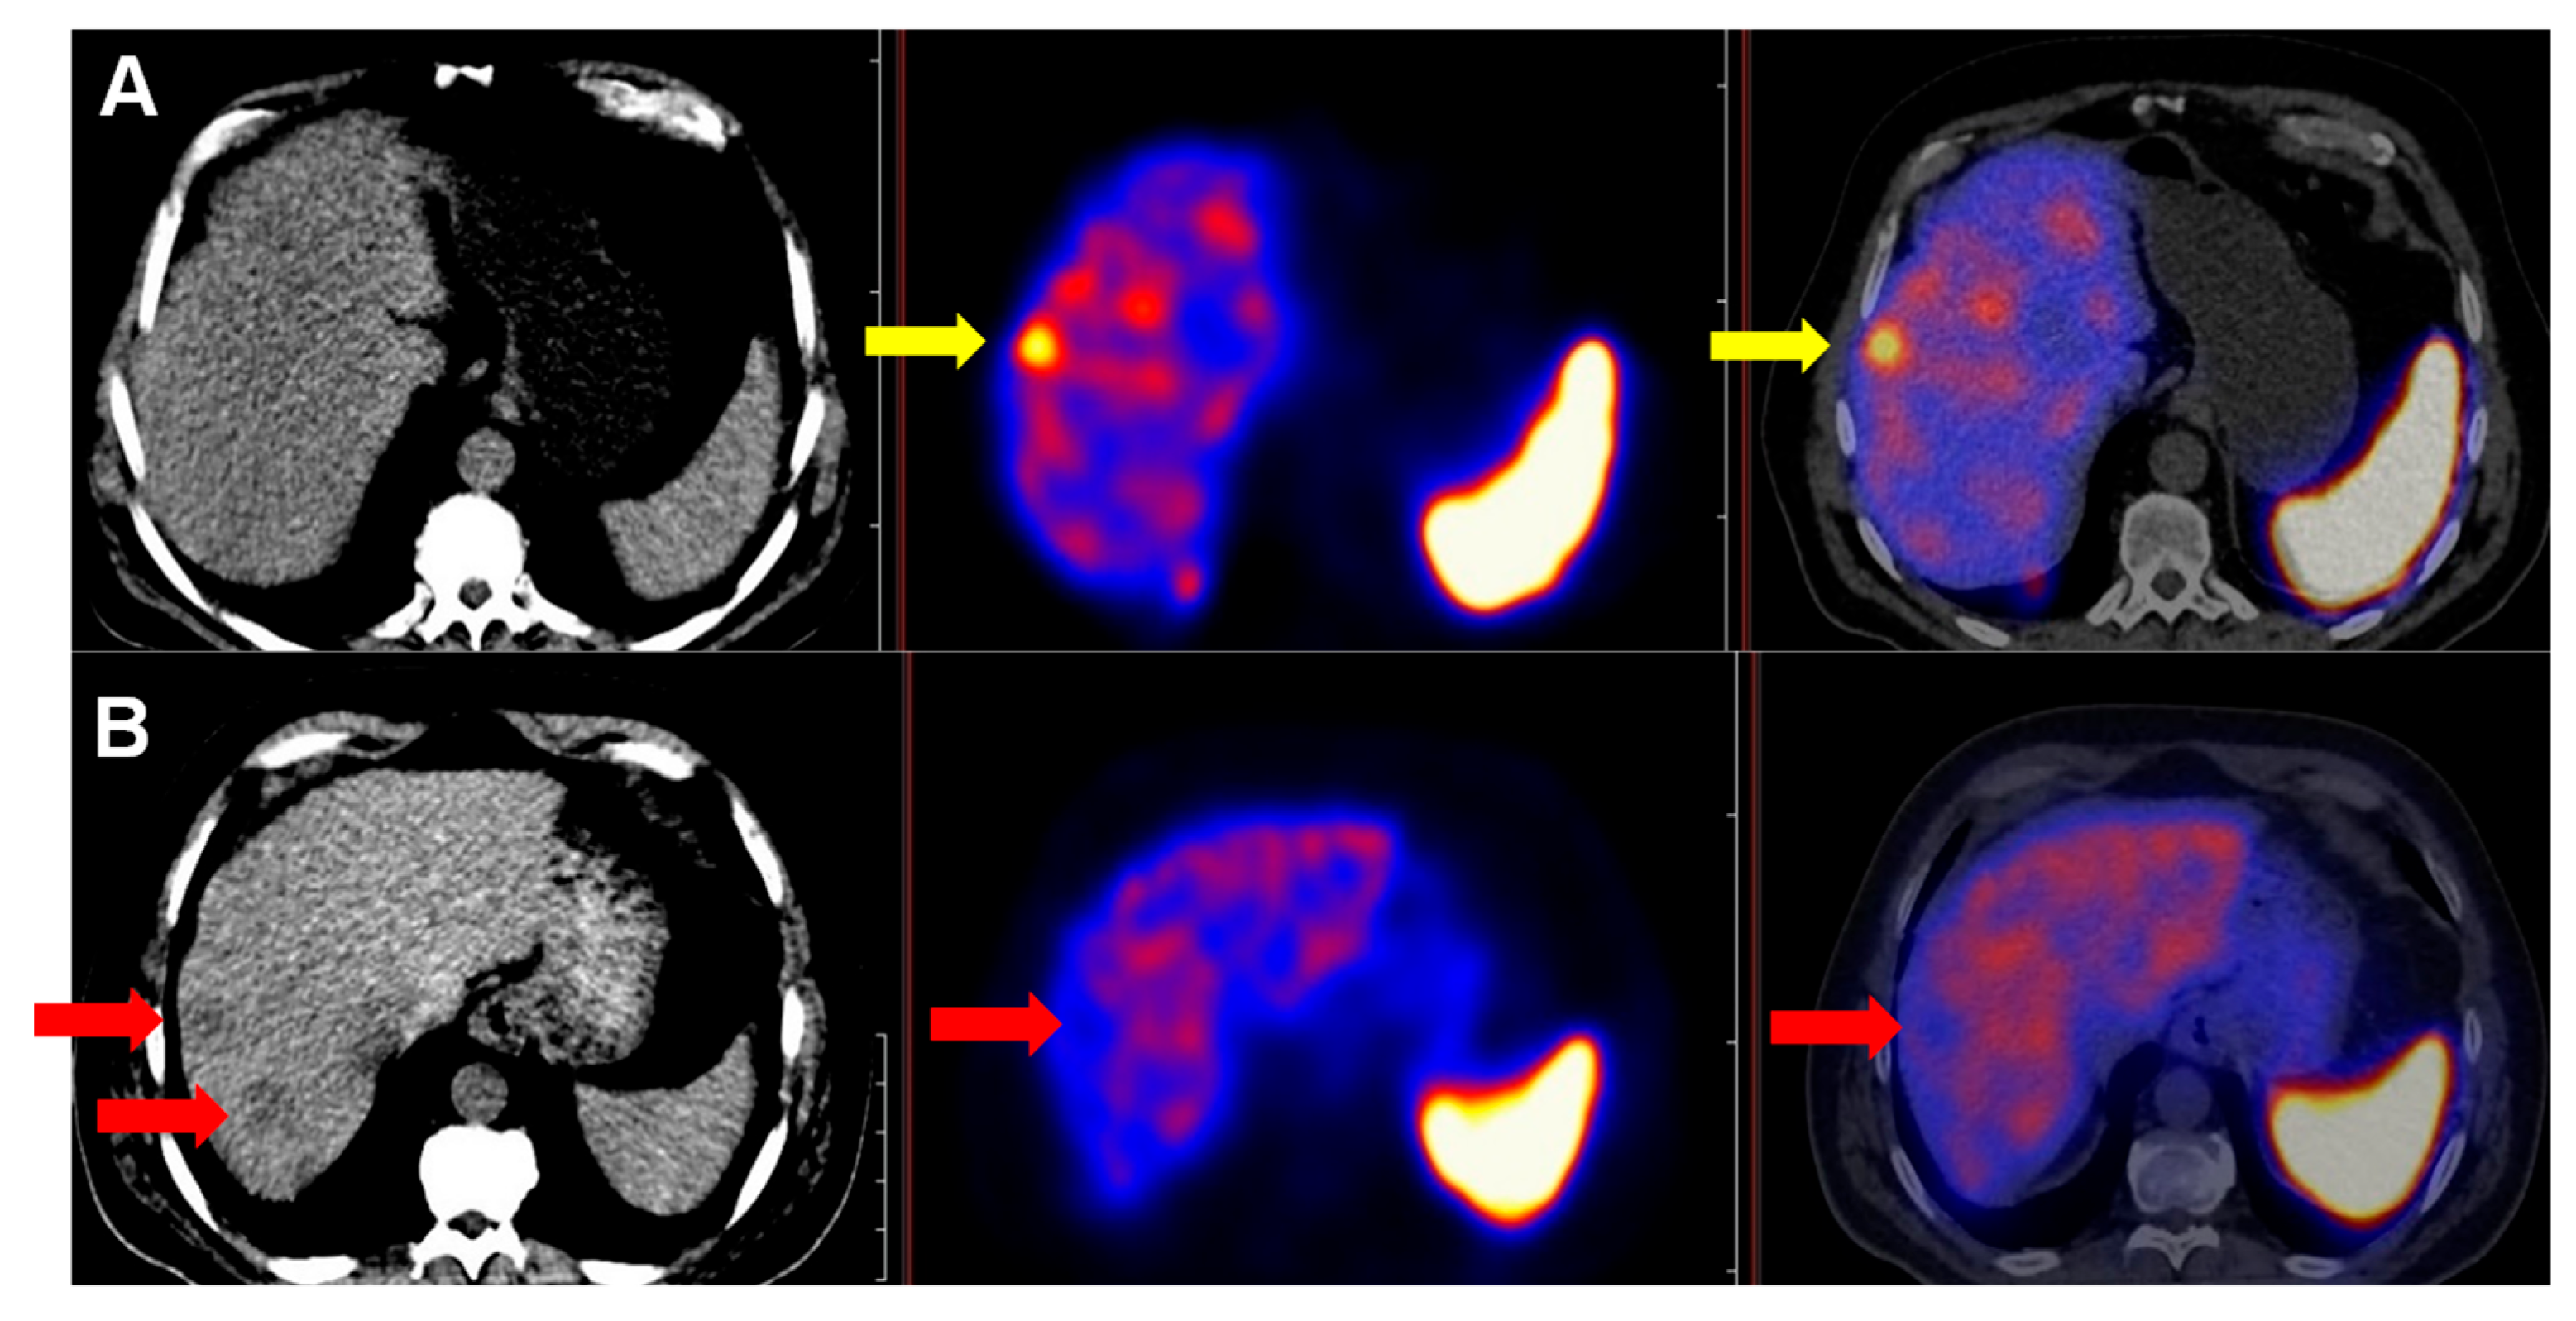

2.3. Image Analysis and Lesion Detection

3.1. Metastatic Neuroendocrine Neoplasms Frequently Exhibit PRRT-Suitable Lesions